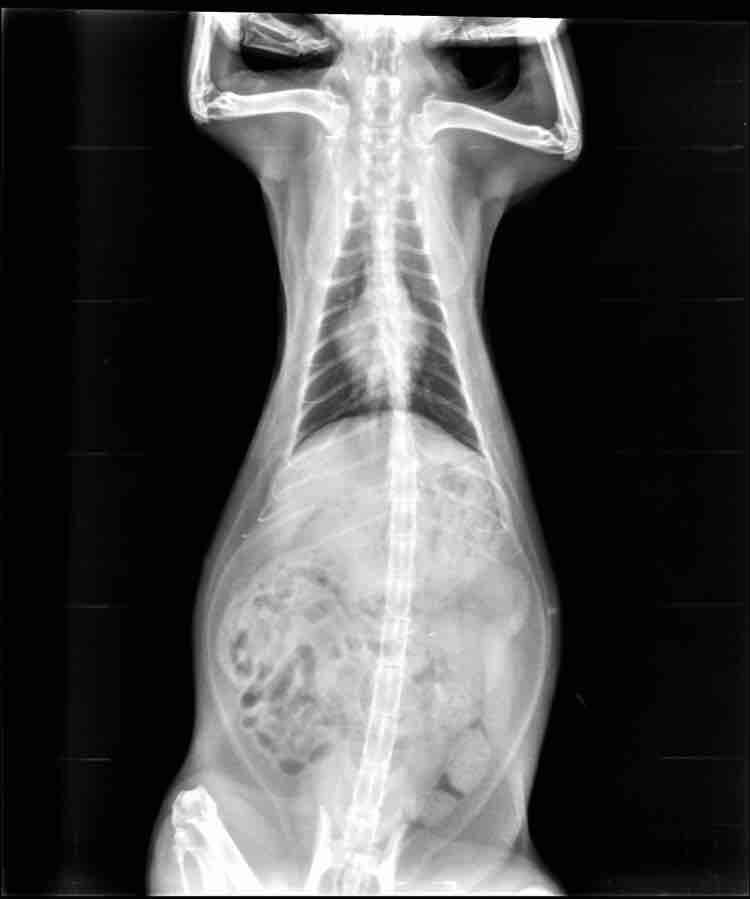

Pet's info: Cat | Mixed Breed | Female | 5 years and 10 months old

Why is her belly so big? Is she just fat? She doesn’t really exercise.

She is most definitely overweight (fat pad can be clearly seen in front of the back legs / below the abdomen). If she has any additional clinical signs I would recommend a blood test to help determine if the obesity is triggered by any medical condition or even if it has caused any problems such as liver issues. I strongly recommend you start a weight management programme such as hills metabolic or royal canin satiety to help reduce the weight (and with it risks of obesity, joint and inflammatory conditions linked with excess weight)